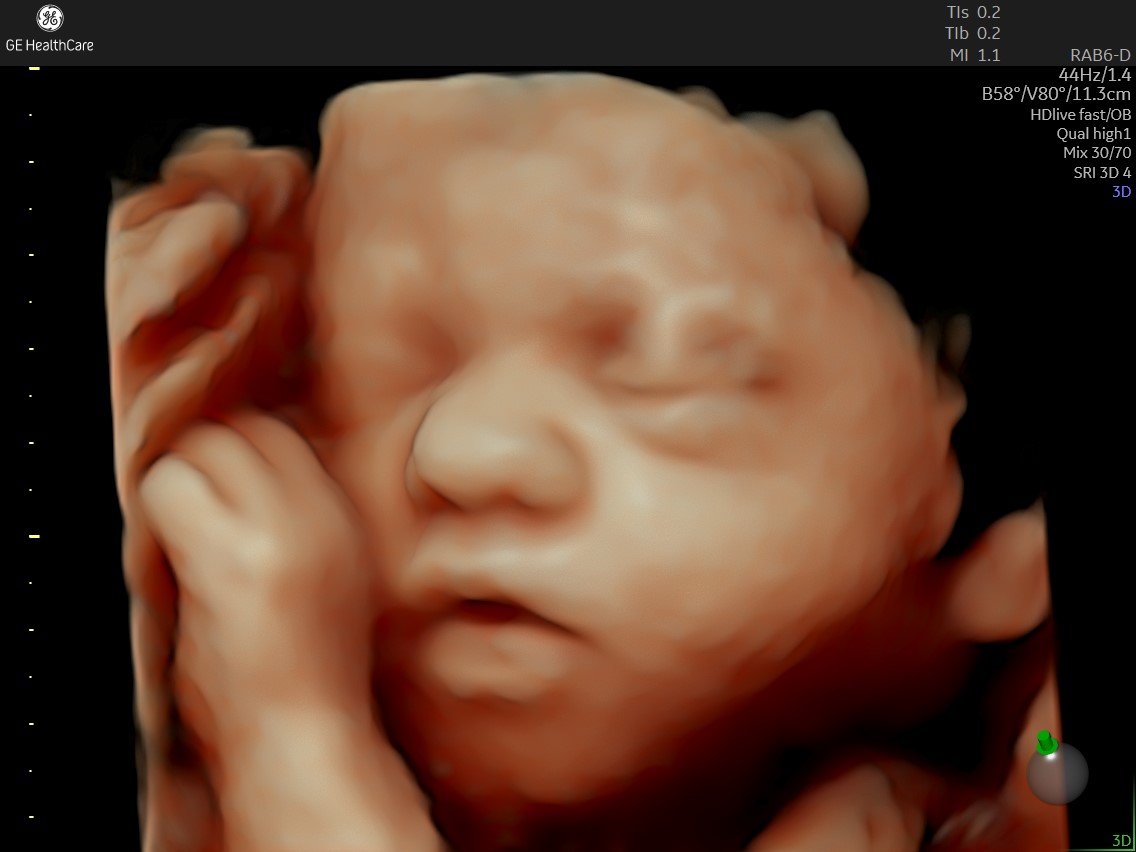

当院はクリニックのため分娩はできませんが、セミオープンシステム(分娩先の病院を予約した上で当院で妊婦健診を行うこと)、里帰り出産をされる方が帰省なさるまでの妊婦健診をさせていただくことができます。3D/4Dエコーももちろん行っております。

3D/4Dエコー

当院では、GE社の最新の超音波機器を導入しており、赤ちゃんとのタイミングが合えばとてもクリアに様々な表情をご覧いただくことができます。

お写真のサンプルはこちらをご覧ください。